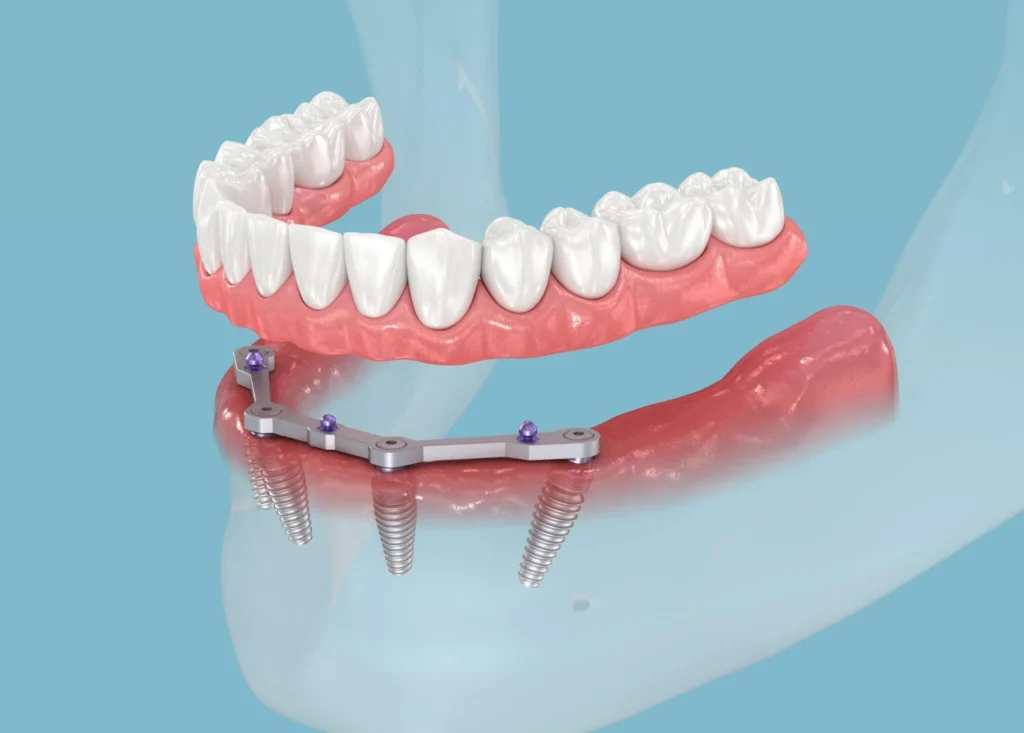

İşlem günü, gerekli diş çekimleri yapılır ve çeneye toplam dört implant yerleştirilir. Arka bölgelerde yer alan implantlar belirli açılarla konumlandırılır. Bu yöntem, kemik grefti ihtiyacını azaltabilir. Tedavinin sonunda geçici bir sabit protez yerleştirilir. Böylece hasta aynı gün içerisinde konuşabilir, gülebilir ve temel çiğneme fonksiyonlarını kazanabilir.

- Dört implantın uygun açılarla yerleştirilmesi

Yaklaşık 3–4 ay sonra implantların kaynaşmasıyla birlikte kalıcı sabit protez uygulanır. Bu süreçte ağız ve diş sağlığının korunması, implantın başarılı şekilde iyileşmesine katkı sağlar. Diş yüzeylerinde oluşan plak birikimini önlemek için düzenli temizlik önemlidir.